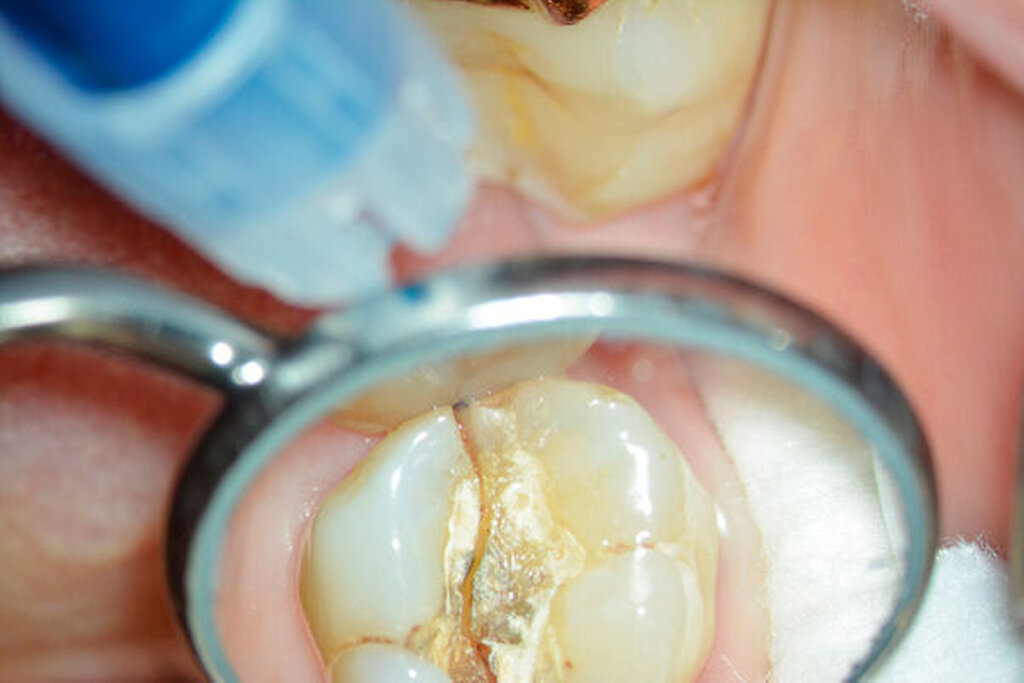

Anschließend verwenden wir eine Lindemannfräse (H162SL, Firma Komet Dental, Lemgo) in einem Schnelllaufwinkelstück und trennen die Wurzel mitsamt des Kronenanteils vorsichtig entlang der zuvor angezeichneten Linie ab. Um den zu erhaltenden Zahnanteil nicht unbeabsichtigt mit der Fräse zu beschädigen, bleibt die Orientierungslinie zunächst unangetastet (Abbildung 1b).

Eine 54-jährige Patientin stellte sich 2018 in der Praxis vor, nachdem sie beim Essen ein Goldinlay an Zahn 16 verloren hatte. Sie klagte über eine Aufbissempfindlichkeit des Zahnes sowie über das Gefühl einer Lockerung. Klinisch zeigte sich eine tiefe Fraktur des Zahnes in mesiodistaler Richtung. Nach klinischer und röntgenologischer Diagnostik wurde die Patientin über die Möglichkeit der Extraktion mit anschließender prothetischer Versorgung der Lücke und den aufwendigen Erhaltungsversuch mittels endodontischer Behandlung des Zahnes samt Amputation der palatinalen Wurzel aufgeklärt. Die Patientin war sehr motiviert und entschied sich für den Erhaltungsversuch.